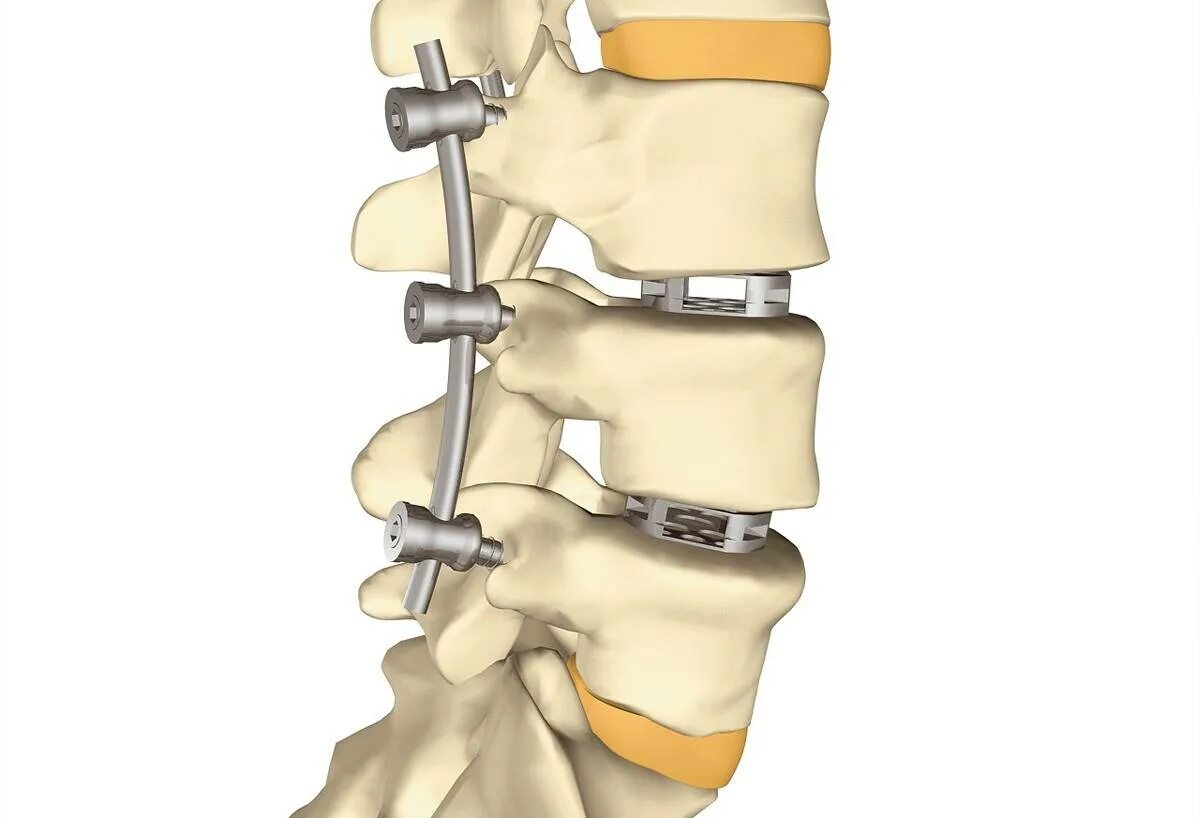

Операция по удалению грыжи шейного отдела